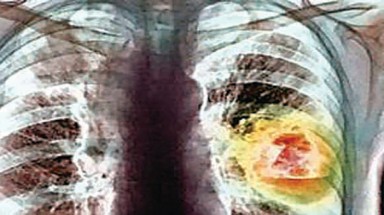

(08:43:34 AM 25/10/2011)(Tin Môi Trường) - (Tinmoitruong.vn) -Theo tạp chí Lancet Oncology, TG4010- một loại thuốc dạng chích chống ung thư phổi qua thử nghiệm ở 148 bệnh nhân đã cho kết quả khả quan. Sau 6 tháng thử nghiệm loại thuốc do Đại học Strassbourg (Pháp) điều chế, người ta thấy 43% bệnh nhân có thuyên giảm so với 35% chỉ dùng hóa trị.

Từ khóa liên quan: ra đời, thuốc, chống, ung thư phổi -